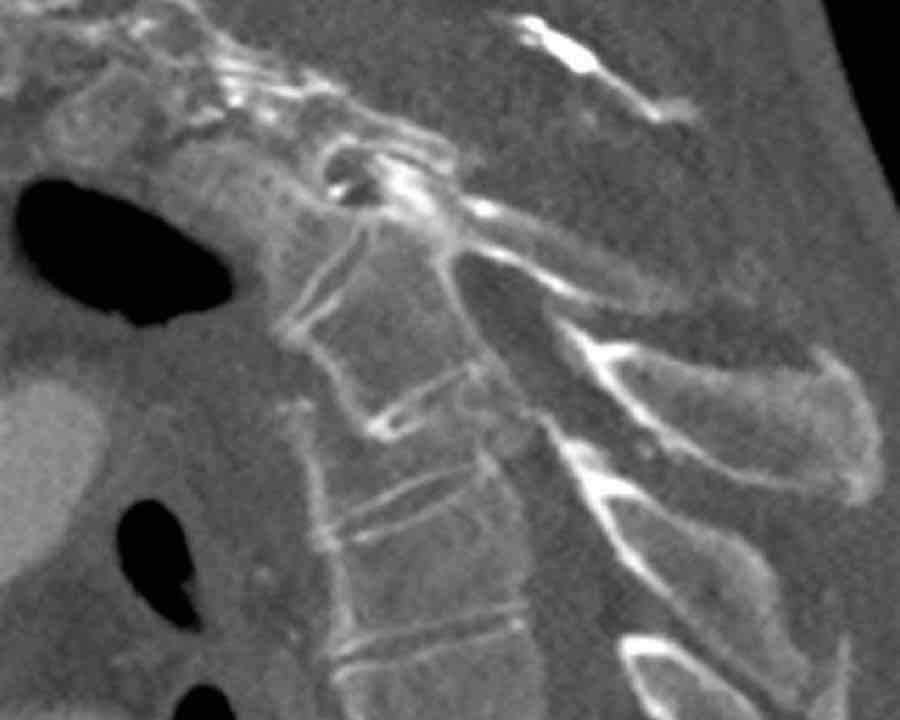

Scroll through the images

Findings:

- Perched facet joints (yellow curved arrows), so think of C injury.

- Posterior displacement of the vertebral bodies in the midline.

- Secondary A4 injury of the vertebral body.

Conclusion

Type C + A4 injury